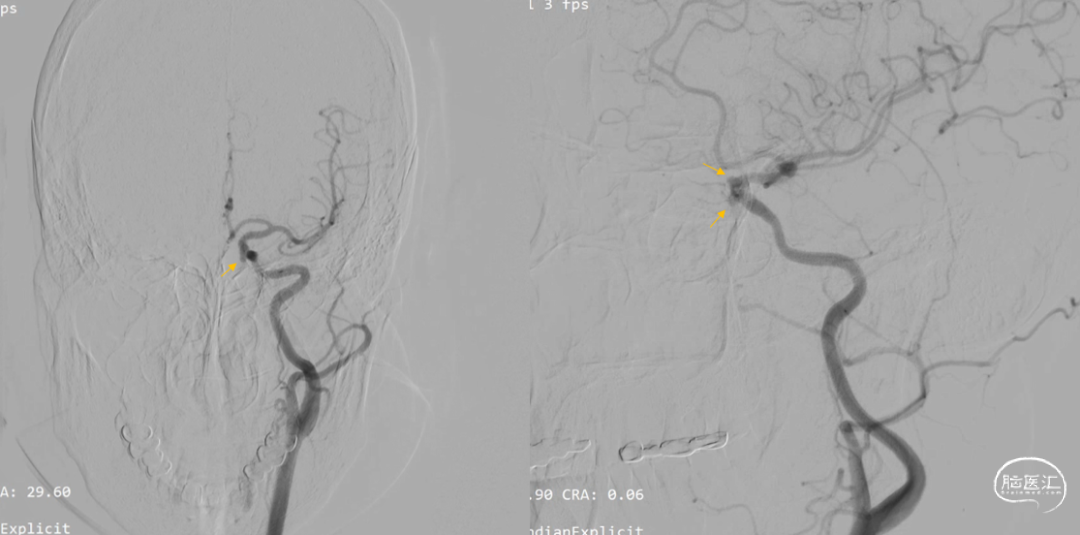

左侧颈内动脉多发动脉瘤

1:C6段,大小约2.9mm×2.0mm×1.3mm、瘤颈宽2.9mm;

2:C6段,大小约3.6mm×3.5mm×2.2mm、瘤颈宽2.9mm;

3:C5段:大小约3.5mm×3.3mm×2.4mm,瘤颈宽5.0mm;

造影显示动脉瘤内造影剂滞留

Vaso I.A. CT检查,支架完全打开,位置及贴壁良好,动脉瘤内部分造影剂滞留